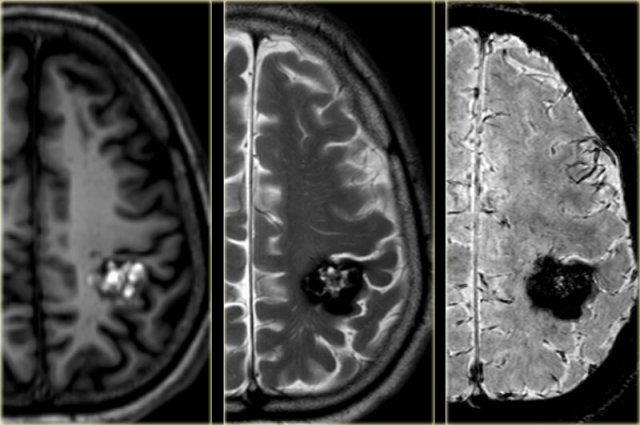

Cavernoma

Cavernoma còn được gọi là dị dạng hang (cavernous malformation) hoặc u mạch hang (cavernous angioma).

Đây là dị dạng mạch máu dòng chảy thấp, lành tính, có xu hướng chảy máu.

75% trường hợp xuất hiện dưới dạng tổn thương đơn độc, tản phát và 10-30% xuất hiện dưới dạng tổn thương đa ổ.

Cavernoma bao gồm các tiểu thùy có kích thước khác nhau chứa các sản phẩm máu ở nhiều giai đoạn tiến triển khác nhau, tạo nên hình ảnh đặc trưng “bỏng ngô” (popcorn).

Một vành hemosiderin hoàn chỉnh bao quanh tổn thương, ngoại trừ trường hợp có chảy máu gần đây.

CT không tiêm thuốc cản quang có thể cho thấy một nốt tăng tỷ trọng hoặc vôi hóa, nhưng trong 50% trường hợp, cavernoma sẽ không được phát hiện trên CT.

Chuỗi xung T2W và T2* gradient echo cho thấy nhiều cavernoma.

Lưu ý hình ảnh “bỏng ngô” với vành hemosiderin ngoại vi trên chuỗi xung T2W.

Các tổn thương gần như hoàn toàn màu đen trên chuỗi xung gradient echo do xảo ảnh blooming.

Chuỗi xung T2* và hình ảnh trọng số độ nhạy từ (SWI) làm tăng đáng kể độ nhạy của MRI trong việc phát hiện các cavernoma nhỏ.

Năm chấm đen ở bán cầu đại não trái trên chuỗi xung T2* cũng là cavernoma và không thể nhìn thấy trên chuỗi xung T2W.

Cavernoma ở hồi sau trung tâm trên chuỗi xung T1W, T2W và SWI.

Lưu ý hình ảnh “bỏng ngô” và xảo ảnh blooming.